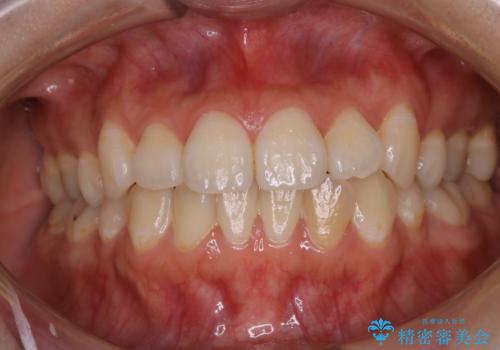

インビザラインでの矯正治療前にPMTCで歯のクリーニング

- 矯正治療の前にクリーニング希望で来院されました。PMTC30分コースを行いました。

PMTCは、国家資格取得者の歯科衛生士により、専門的な機械や材料を使用してのクリーニングです。一人一人の患者様のお口の状態に合わせたクリーニングを行います。

矯正治療は、歯を動かすため歯肉にも負担がかかります。そのため、矯正前にしっかりクリーニングを行い健康なお口の状態にしておくことが大切です。